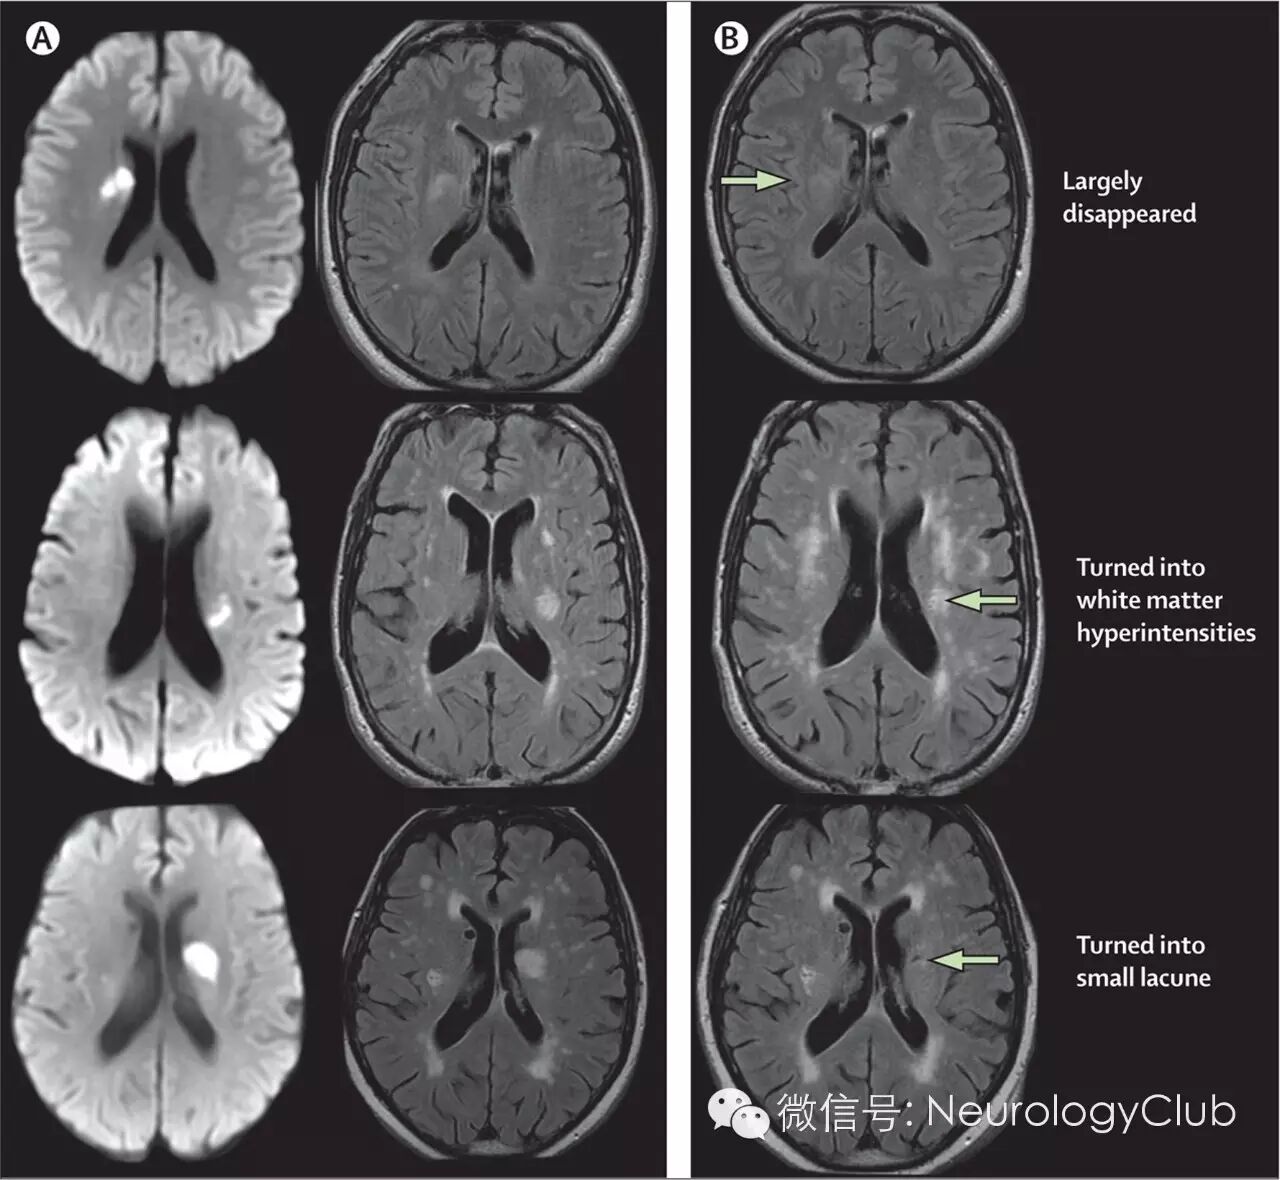

(急性小梗死的晚期常见结局。A:急性期的DWI[左]和FLAIR[中];B:1年后的FLIR。这些小梗死可消失,或表现为白质高信号或空洞化演变为腔隙)